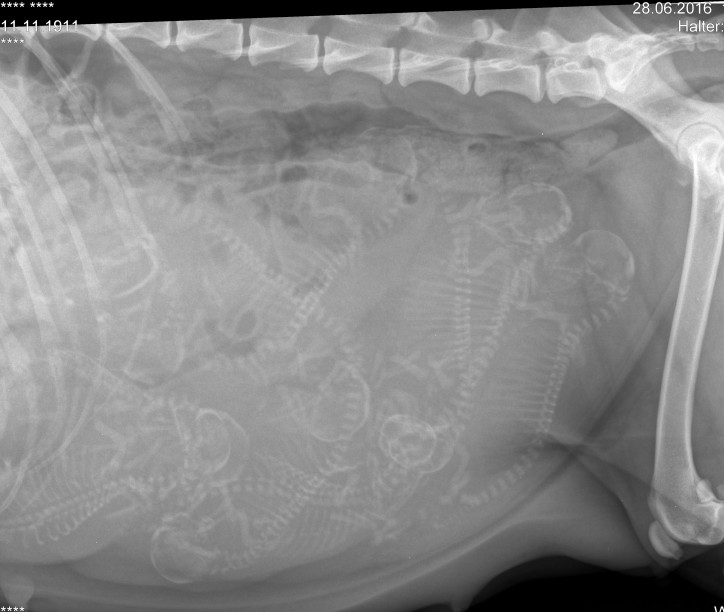

Ich war heute mit Toffee beim Röntgen um zu schauen wie es aussieht, wir haben viele Baby's zählen können

ich freue mich riesig auf meinen C-Wurf